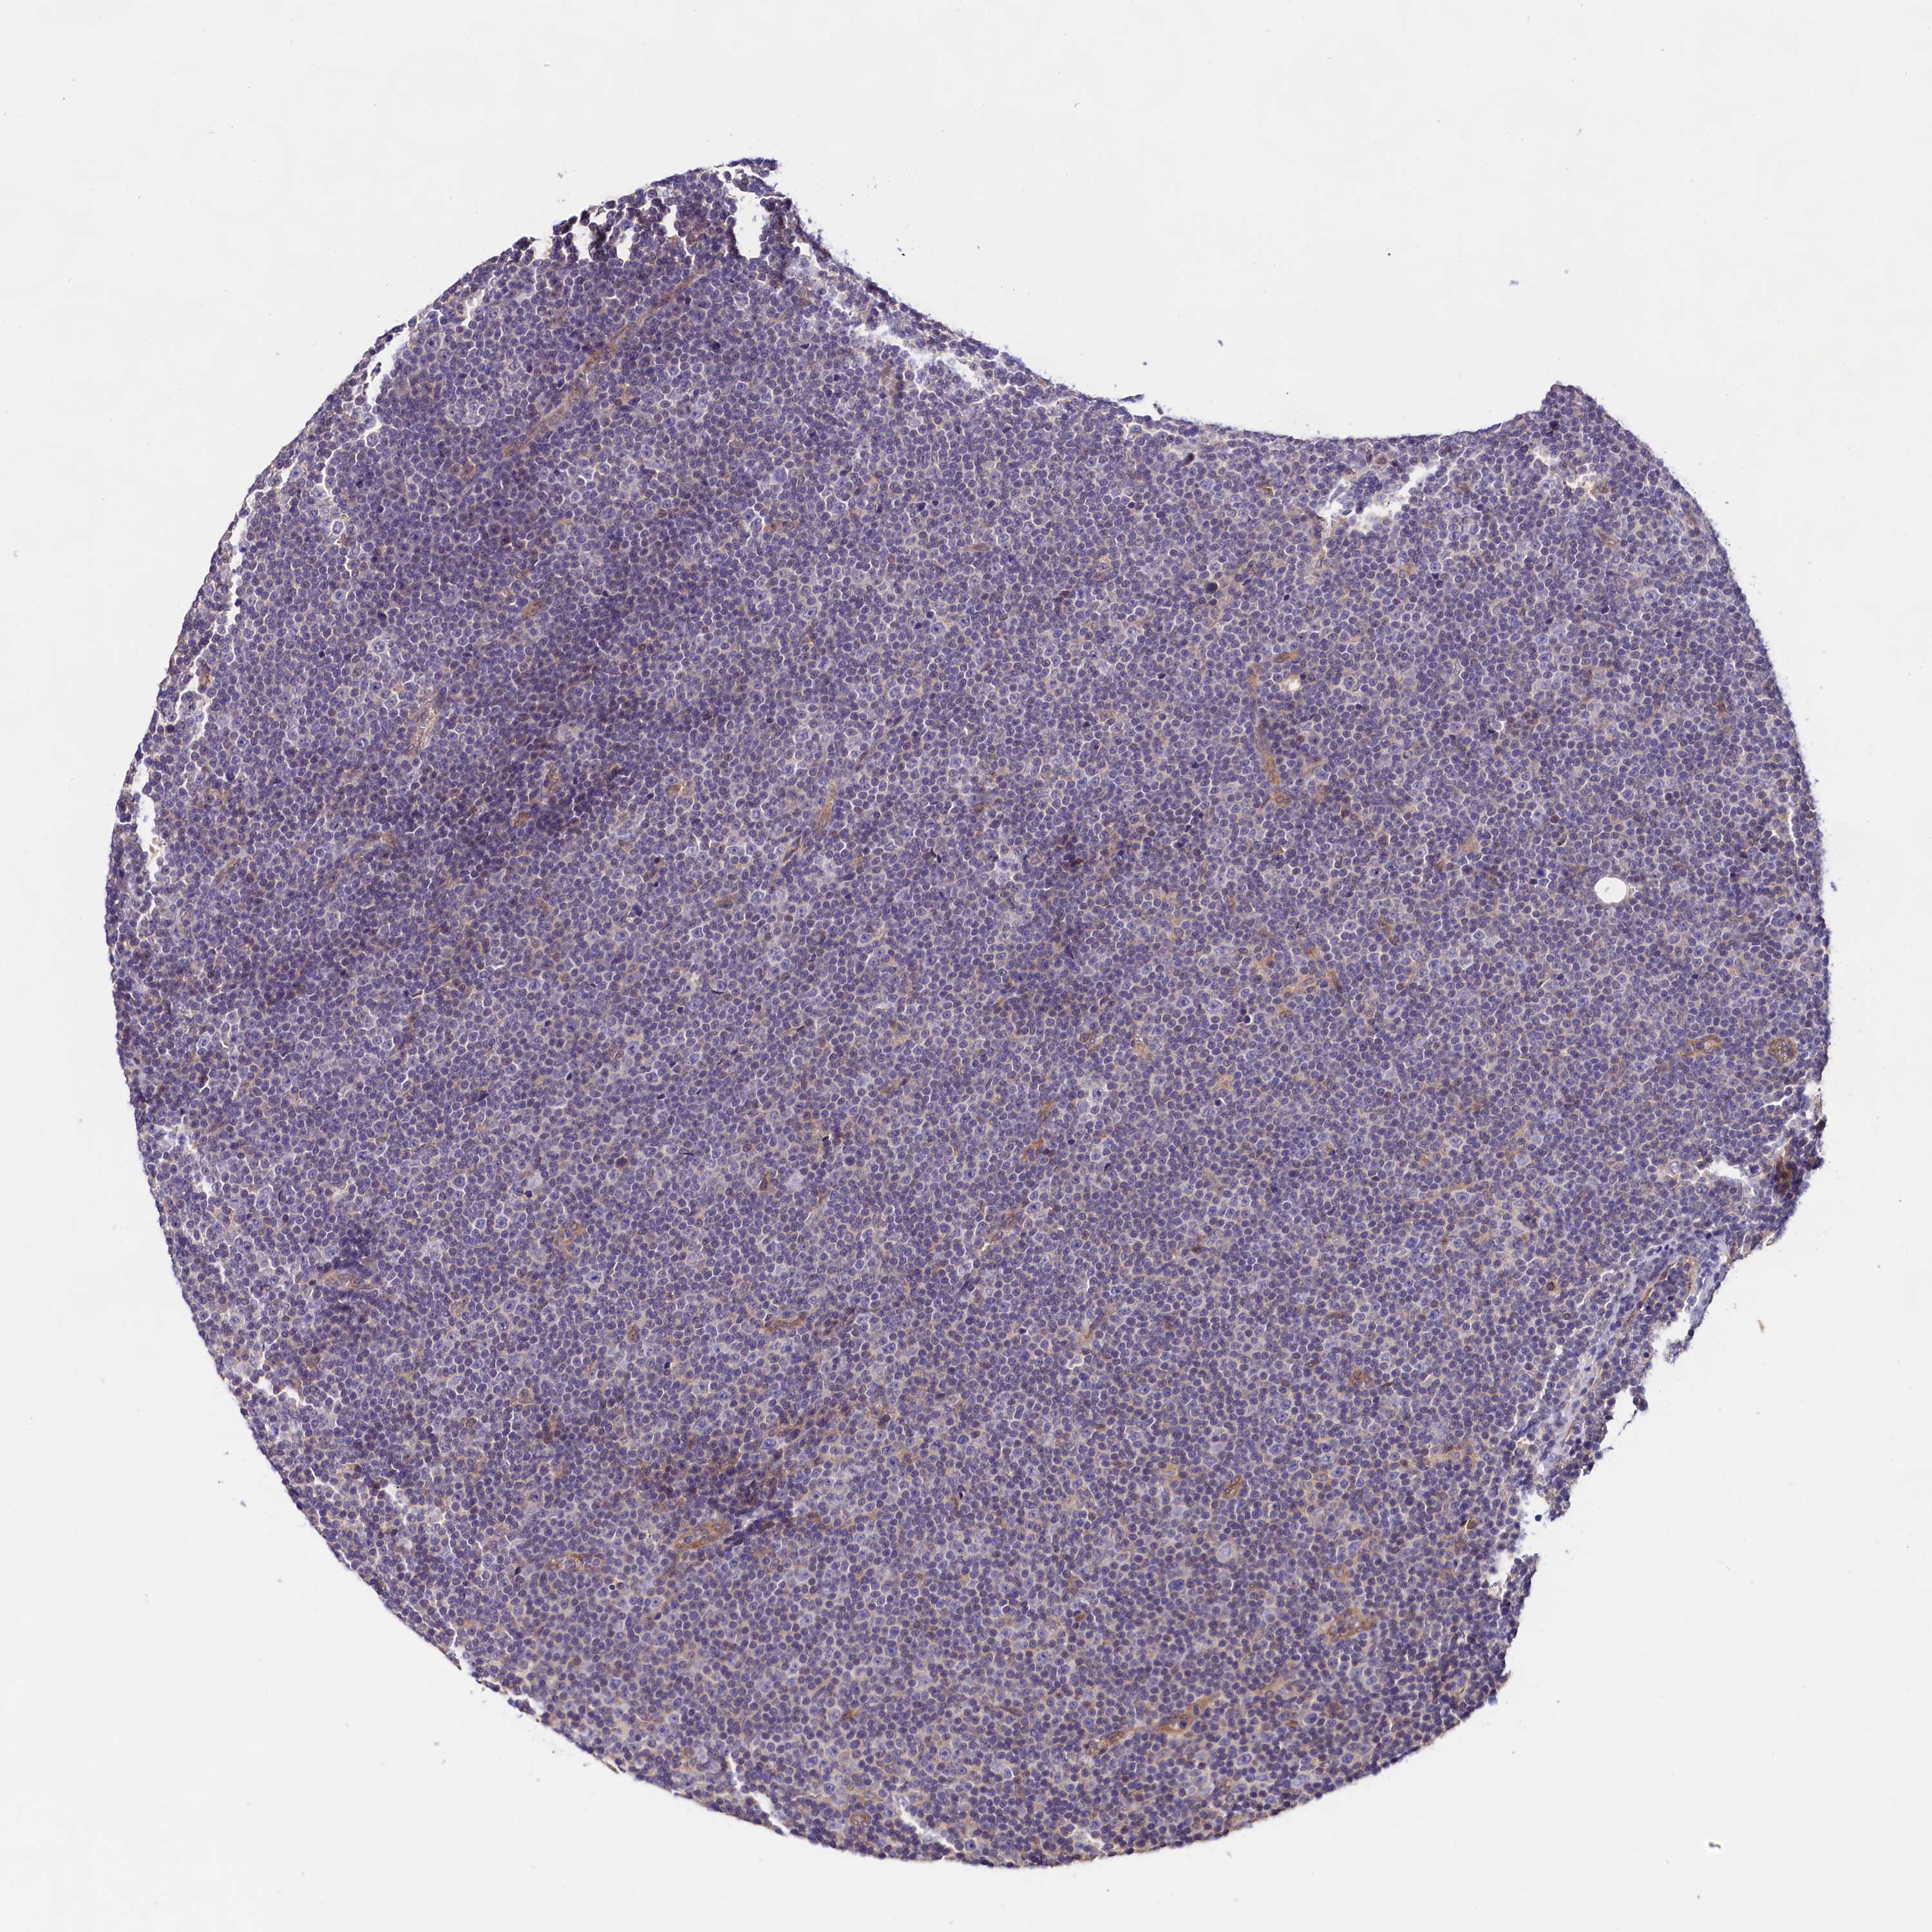

LYMPHOMA - Protein expressioni

A mouse-over function shows sample information and annotation data. Click on an image to view it in a full screen mode. Samples can be filtered based on level of antibody staining by selecting one or several of the following categories: high, medium, low and not detected. The assay and annotation is described here.

Antibody stainingi

Antibody staining in the annotated cell types in the current human tissue is reported as not detected, low, medium, or high, based on conventional immunohistochemistry profiling in selected tissues. This score is based on the combination of the staining intensity and fraction of stained cells.

Each image is clickable and will lead to virtual microscopy that enables deeper exploration of all samples and also displays staining intensity scores, fraction scores and subcellular localization as well as patient and tissue information for each sample.

Antibody HPA041253

Antibody HPA041372

Staining

High

Medium

Low

Not detected

Intensity

Strong

Moderate

Weak

Negative

Quantity

>75%

75%-25%

<25%

None

Location

Nuclear

Cytoplasmic/membranous

Cytoplasmic/membranous,nuclear

Hodgkin's disease, NOS

Malignant lymphoma, non-Hodgkin's type, Low grade

Malignant lymphoma, non-Hodgkin's type, High grade